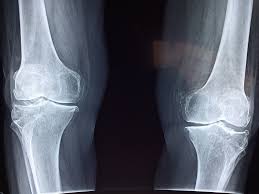

Prenez soin de votre capital osseux

Un point rarement abordé : l’effet des sodas, et surtout des colas, sur la santé de nos os. Le souci ne tient pas à un seul ingrédient, mais plutôt au fait qu’ils prennent souvent la place de boissons riches en calcium, comme le lait ou les laits végétaux enrichis. Pour les ados et jeunes adultes, cela peut nuire à l’édification d’une ossature solide. Chez les plus âgés, cela contribue à un affaiblissement osseux progressif.